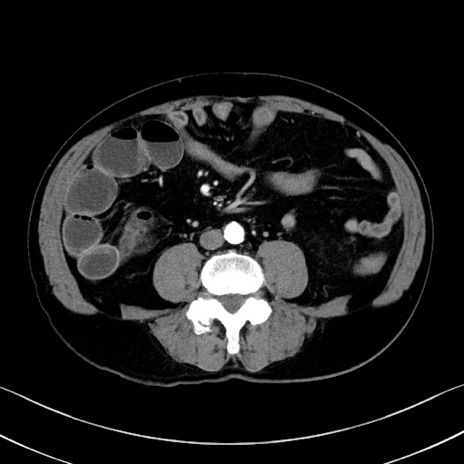

冠状断像

【症例】70歳代 男性

【主訴】腹部膨満、嘔吐

【現病歴】昨日より腹部膨満感出現。本日増悪し、仙痛出現。嘔吐あり、受診。

【既往歴】糖尿病、胆摘後

【身体所見】BP 149/80mmHg、HR 74/min、BT 35.9℃、腹部:膨満、軟、圧痛なし。腸雑音減弱あり。上腹部正中切開瘢痕あり。

【データ】WBC 13500、CRP 1.72